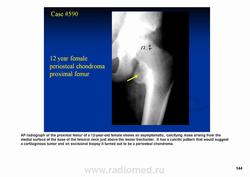

Периостальная хондрома (син.: юкстакортикальная хондрома, паростальная хондрома редкая доброкачественная опухоль, состоящая из зрелой хрящевой ткани и расположенная над надкостницей. Обычно она разрушает наружную часть коркового слоя, но не прорастает в костно-мозговой канал. Мужчины болеют в два раза чаще женщин. Типичная локализация - проксимальный конец плечевой и бедренной кости дистальный конец бедренной кости, а также фаланги. В редких случаях одновременно поражается несколько костей. Периостальная хондрома обнаруживается большей частью в метафизарной части, лишь у 30 % больных поражаются диафизы. Опухоль достигает в среднем 2-3 см в диаметре. Она окружена зоной остеосклероза и сопровождается периостальным остеогенезом, так что на границе опухоли с костью образуется грушевидное углубление с четкими контурами. Под микроскопом периостальная хондрома имеет тонкие контуры, она как бы погружена в корковый слой и покрыта надкостницей, как тонкой скорлупой. На разрезе ее ткань синюшно-серая или белая, хрящевые элементы обладают дольчатым строением. Участки обызвествления имеют вид желтовато-белых вкраплений. Эта опухоль состоит из гиалинового хряща, дольки которого разделены фиброзными прослойками или костными балками, местами обызвествленными. Кое-где отмечается проникновение опухолевых клеток в костномозговой канал, на большем же протяжении внутренний контур образован компактной костью.

Дифференциальная диагностика представляет известные трудности в тех случаях, когда периостальная хондрома имеет сходство с юкстакортикальной хондросаркомой.